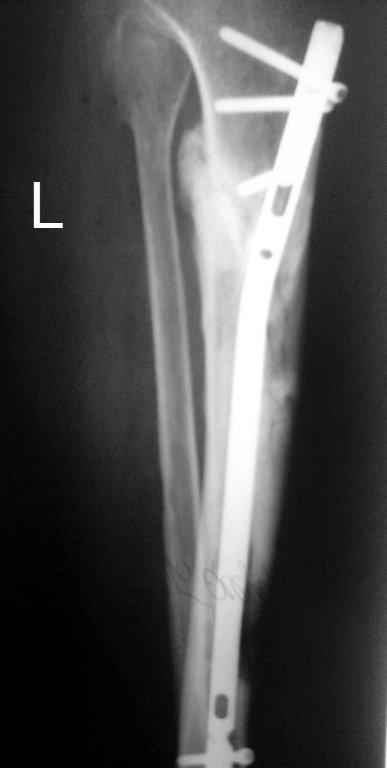

Тогда можно рассмотреть вопрос одновременного удаления штифта, мышечной (в данной области применим проксимально отсеченный лоскут камбаловидной мышцы) или микрохирургической (что более надежно) пластики дефекта мягких тканей, остеотомии проксимального фрагмента большеберцовой кости, остеосинтеза блокируемым штифтом с а/б покрытием, наложения простого аппарата Илизарова (можно из полуколец) для дистракции на штифте. При данном варианте пациент сохраняет возможность полной опоры на ногу, что очень важно для заживления у пожилого пациента) и отпадает необходимость в проведении дополнительный операций (при благоприятном развитии событий).

Выкладываю картинки похожей пациентки. Извините, что без окончательных снимков (сейчас их нет под рукой). Правда мы имели проблемы у данной больной после снятия аппарата, когда промежуточный фрагмент большеберцовой кости сместился на 1,5 см дистально и отошел от проксимальной части кости. До сих пор у пациентки на снимках определяется лишь тонкая полоска кости по задней поверхности за штифтом (образовалось что-то вроде маленького регенерата)в области стыковки промежуточного и проксимального фрагментов. Больная пока решила подождать. Не хочет оперироваться, так как ходит не хромая, работает.